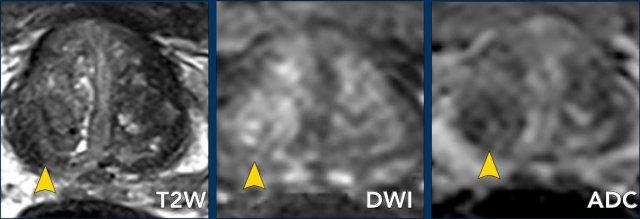

Hãy quan sát hình ảnh trước rồi tiếp tục đọc.

Các phát hiện bao gồm:

- Một tổn thương phân loại đánh giá PI-RADS 4 nằm ở vùng ngoại vi bên trái của phần giữa tuyến tiền liệt.

Giảm tín hiệu rõ rệt khu trú trên ADC (mũi tên vàng) (điểm 4), tương ứng với vùng giảm tín hiệu trên chuỗi xung T2W (điểm 4).

Điểm Gleason của tổn thương này là 3+4.

- Một tổn thương phân loại đánh giá PI-RADS 3 nằm ở vùng ngoại vi bên phải, với giảm tín hiệu khu trú nhẹ trên ADC (mũi tên xanh lá) và đồng tín hiệu trên DWI (điểm 3).

Không thực hiện DCE và không thể phân biệt thêm được.

Sinh thiết không cho thấy bất kỳ dấu hiệu ác tính nào.